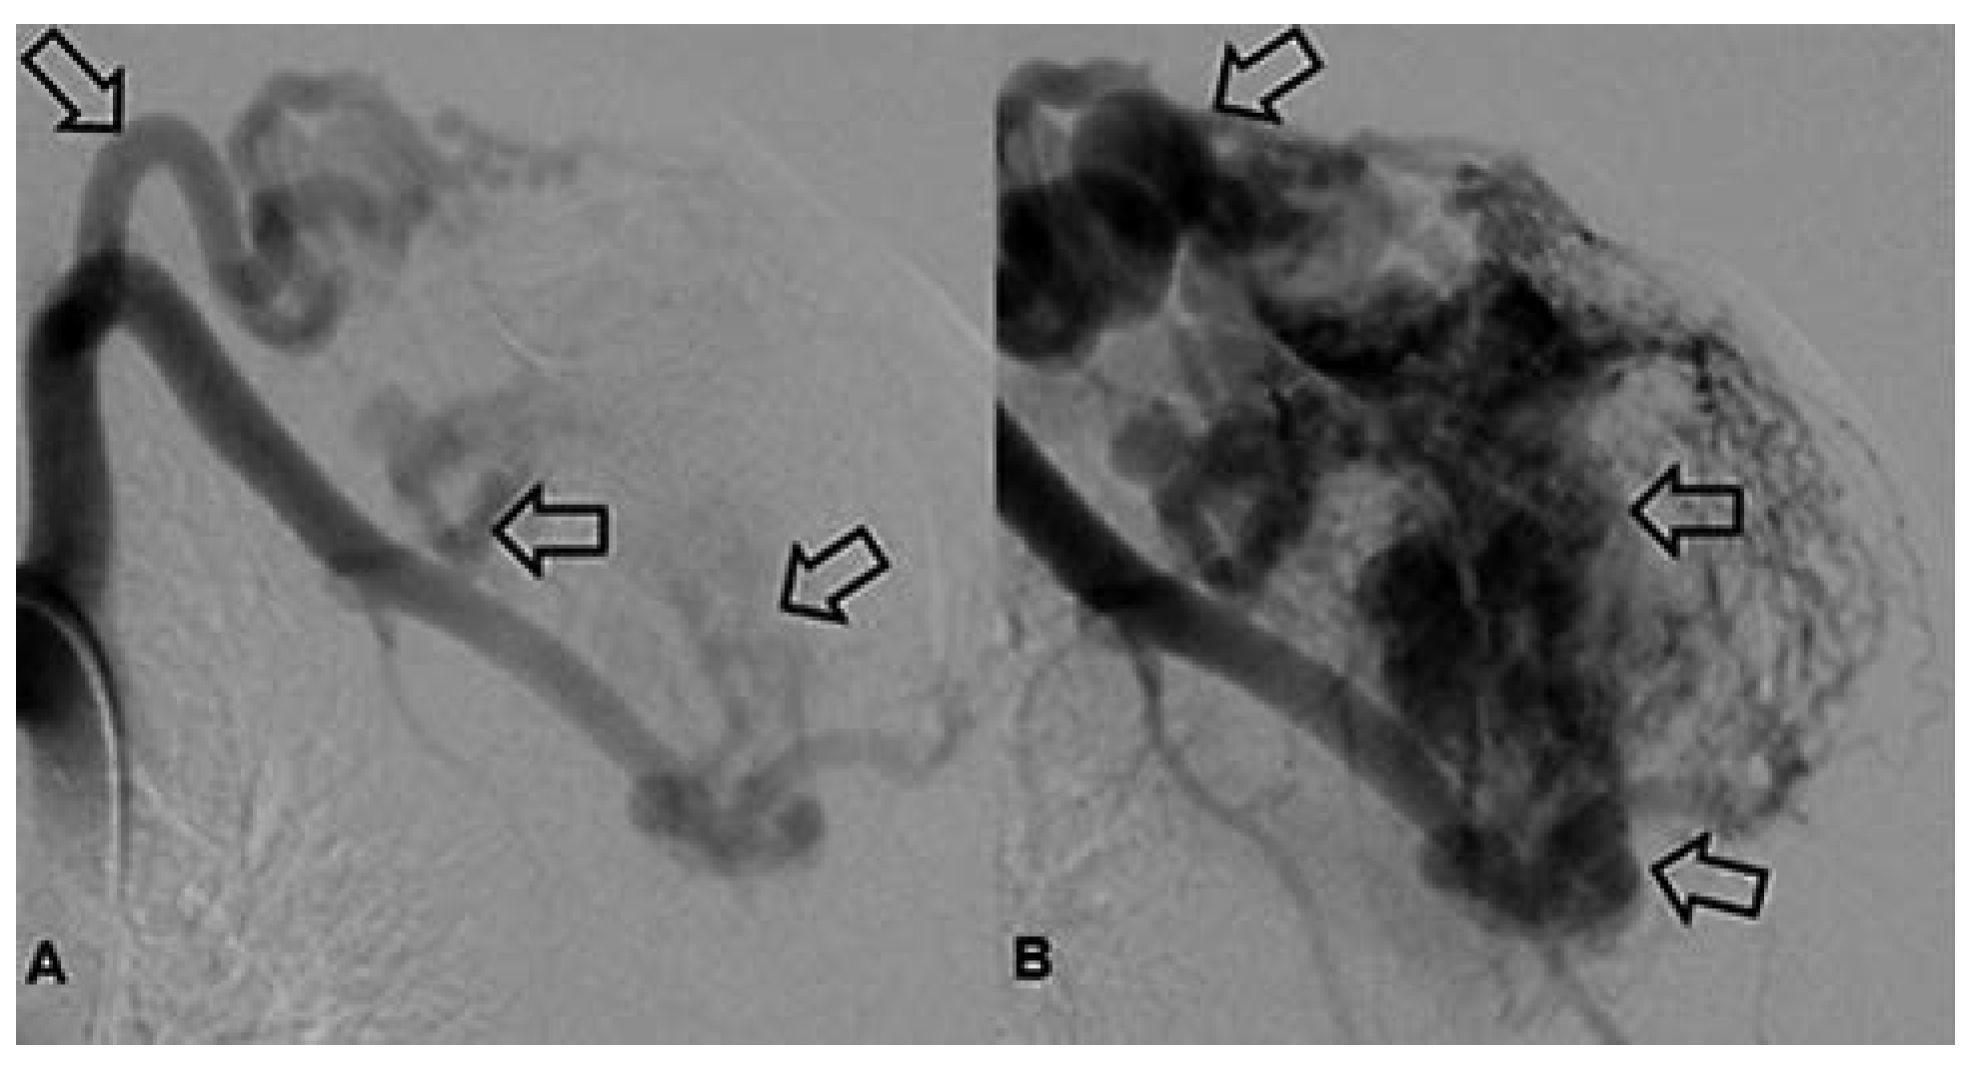

Arteriovenöse Malformation

Arterielle Malformation und arteriovenöse Fistel

- Cho, S.K.; et al. Arteriovenous malformations of the body and extremities: analysis of therapeutic outcomes and approaches according to a modified angiographic classification. J Endovasc Ther. 2006, 13, 527–538. [Google Scholar] [CrossRef]

- Lee, B.B.; et al. Consensus Document of the International Union of Angiology (IUA)-2013. Current concept on the management of arterio-venous management. Int Angiol. 2013, 32, 9–36. [Google Scholar]

- Do, Y.S.; et al. Ethanol embolization of arteriovenous malformations: interim results. Radiology 2005, 235, 674–682. [Google Scholar] [CrossRef]